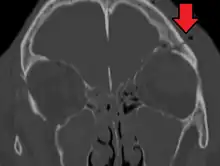

Basilar skull fracture

A basilar skull fracture is a break of a bone in the base of the skull.[1] Symptoms may include bruising behind the ears, bruising around the eyes, or blood behind the ear drum.[1] A cerebrospinal fluid (CSF) leak occurs in about 20% of cases and may result in fluid leaking from the nose or ear.[1] Meningitis occurs in about 14% of cases.[2] Other complications include injuries to the cranial nerves or blood vessels.[1]

A basilar skull fracture typically requires a significant degree of trauma to occur.[1] It is defined as a fracture of one or more of the temporal, occipital, sphenoid, frontal or ethmoid bone.[1] Basilar skull fractures are divided into anterior fossa, middle fossa and posterior fossa fractures.[1] Facial fractures often also occur.[1] Diagnosis is typically by CT scan.[1]

Basilar skull fractures include breaks in the posterior skull base or anterior skull base. The former involve the occipital bone, temporal bone, and portions of the sphenoid bone; the latter, superior portions of the sphenoid and ethmoid bones. The temporal bone fracture is encountered in 75% of all basilar skull fractures and may be longitudinal, transverse or mixed, depending on the course of the fracture line in relation to the longitudinal axis of the pyramid.[5]